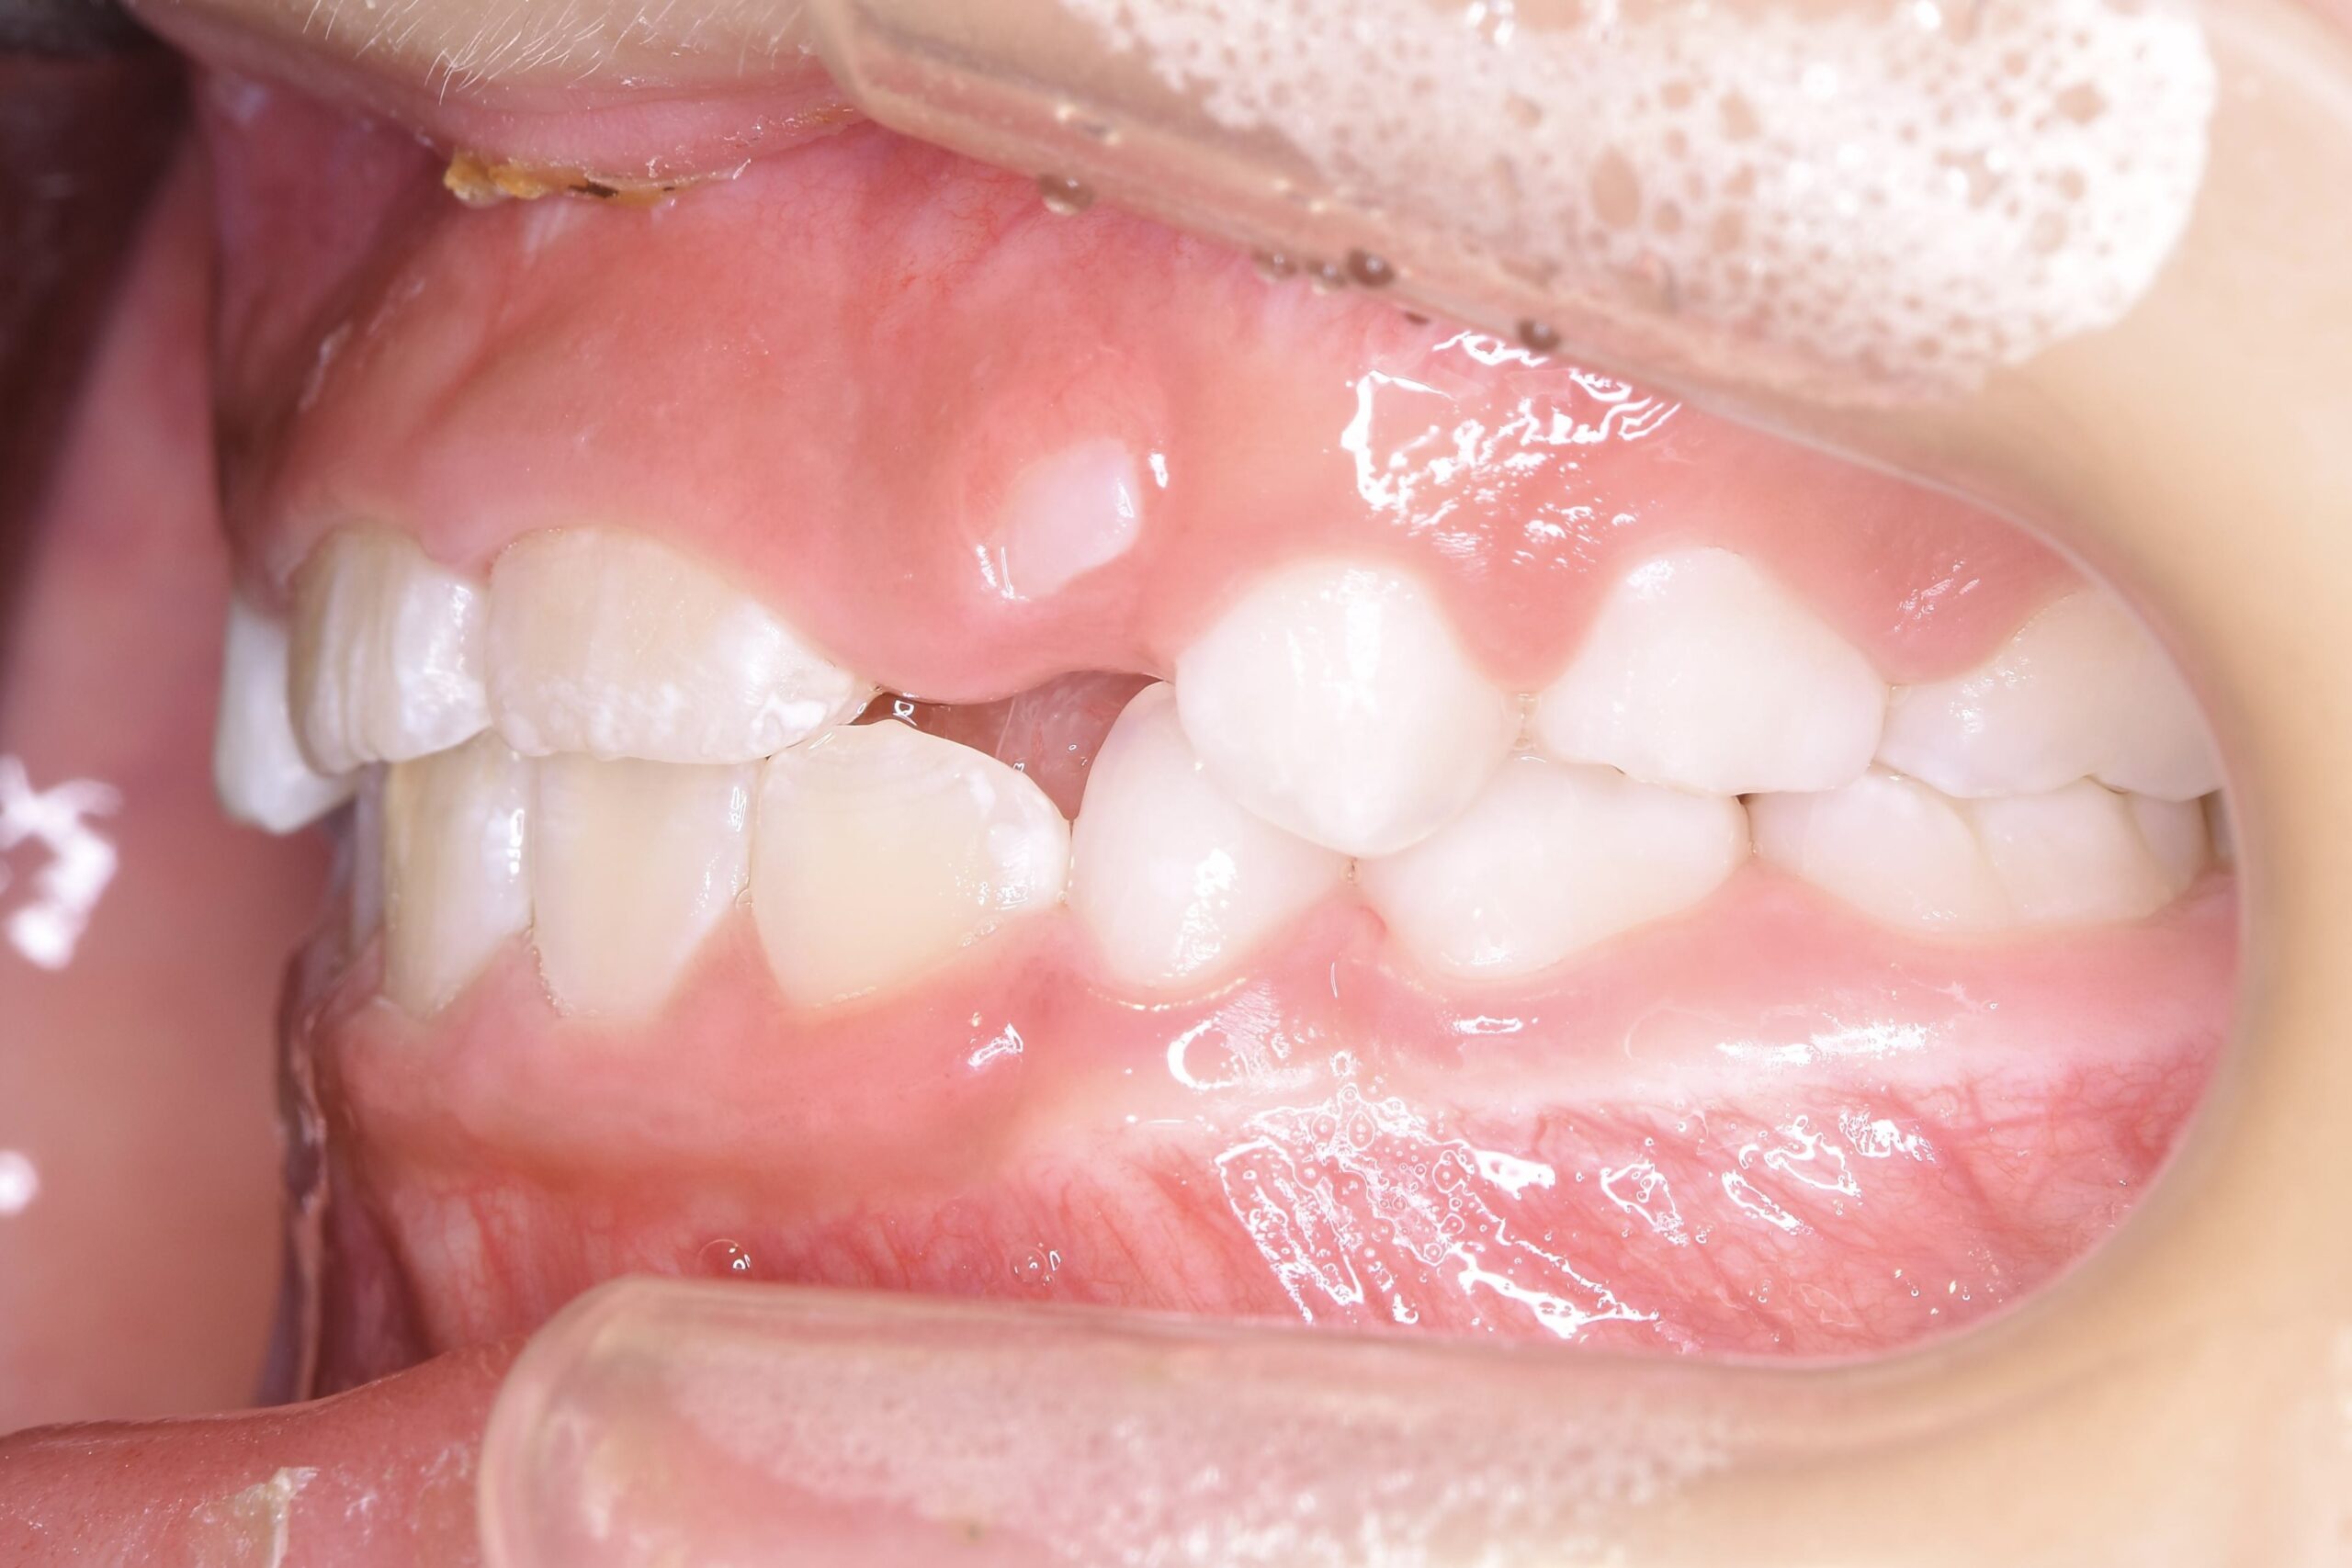

BEFORE

AFTER

主訴

右下の歯が飛び出ているので治したい。

診断名・主な症状

過蓋咬合

治療内容

上下の歯並びの幅を拡げつつ、前歯の関係を改善しました。

使用装置

急速拡大装置

リンガルアーチ

機能的矯正装置(マイオブレース)